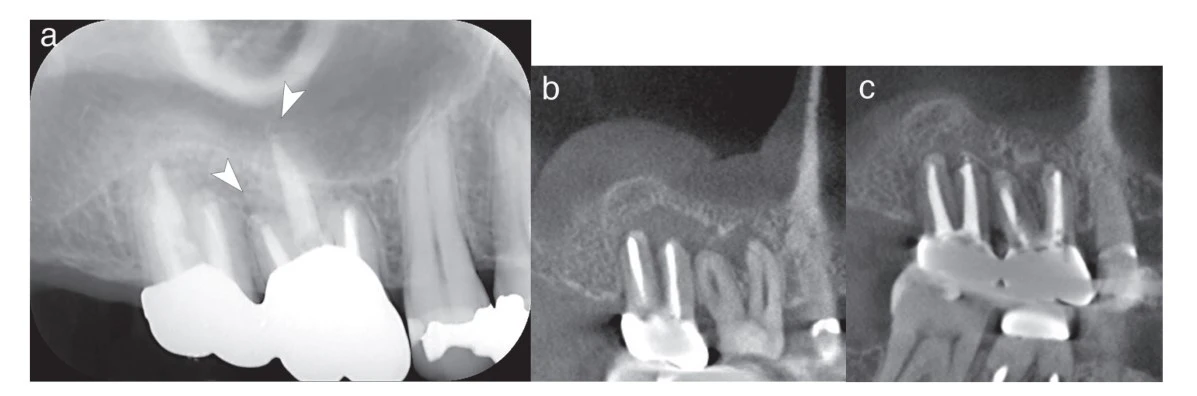

Một nam bệnh nhân, 42 tuổi, có một lỗ thoát mủ liên tục trong nướu khu vực răng hàm trên phía phải đã được giới thiệu từ một phòng nha khoa khác đến chúng tôi.

Qua kiểm tra lâm sàng trong miệng, chụp X-quang trong miệng và chụp cắt lớp vi tính (CBCT), chúng tôi chẩn đoán rằng răng hàm trên thứ nhất và thứ hai của bệnh nhân mắc phải viêm áp-xe quanh chóp mãn tính. Tổn thương áp-xe quanh chóp của cả hai răng đã kết hợp thành nang và vùng chóp ống tủy phía má của cả hai răng cũng nằm trong khu vực tổn thương hợp nhất. Sau quá trình điều trị không phẫu thuật lại ống tủy, chúng tôi đã trám bít với vật liệu thủy tinh sinh học Bioactive Glass (BG Multi) vào ống tủy của cả hai răng bằng kỹ thuật trám bít 1 cone (single cone).

Việc trám bít ống tủy đã được kiểm tra thông qua chụp X-quang trong miệng. So sánh hình ảnh CBCT trước và sau một năm điều trị cho thấy tổn thương áp-xe quanh chóp của cả hai răng đã gần như biến mất. Ngoài ra, sự dày dặn của niêm mạc xoang trên gần răng hàm trên đã cải thiện đáng kể và khu vực này trông bình thường trở lại.

Kết luận: Thành công trong việc điều trị tủy lại mà không cần phẫu thuật đã cho thấy rằng việc trám bít ống tủy bằng chất trám bít ống tủy BG với kỹ thuật trám bít 1 cone (singe cone) là một lựa chọn khả thi.